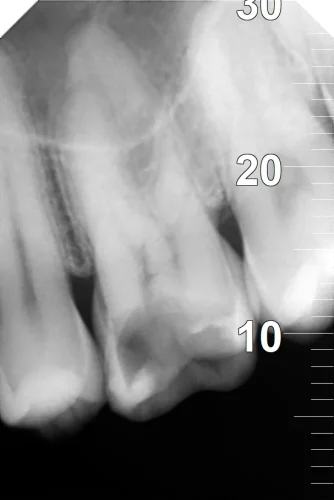

The client had no major health problems; however, she had some previous restorative dental work. He complained that his tooth number 11 has been getting worse within two weeks, mostly induced by hot and cold foods and chewing. During the examination, the dentist found deep decay around the nerve and noted percussion tenderness. Painless treatment was an absolute priority in the case of the patient, as he had unpleasant dental experiences in the past. High-quality 3D imaging was employed to map the tooth structure accurately to achieve a proper course of action.

Pulpitis had been diagnosed to be irreversible with an infection of nerve tissue within tooth number 11. Root canal was prescribed in order to remove the infection and save the tooth. Dr. Ashwin utilized an orthograde procedure, which was non-surgical and helped to clean and shape the root canals with the aid of a thorough 3D imaging. The restoration was to be fabricated with the zirconia crown that is strong in nature and provides the natural biting power. The plan was resourceful in patient comfort and clinical efficiency and cost-effectiveness.

Topical and local anesthesia was done. Tooth number 11 was isolated using a rubber dam and kept sterile. Under the guidance of 3D imaging, Dr. Ashwin excised infected tissues with rotary tools and irrigation with a lot of care. The gutted canals were stuffed with gutta-percha and capped with cement. Proper management of pain secured comfort for the patient. Lastly, the zirconia crown, which was very strong and appealing to the eye, was cemented, and this restored the functionality of the teeth.